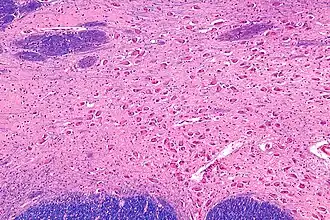

![]() Intermediate magnification micrograph of the nucleus basalis. LFB-HE stain. | |

NBM in relation to the globus pallidus and putamen - very low magnification. -

NBM - very high magnification. -